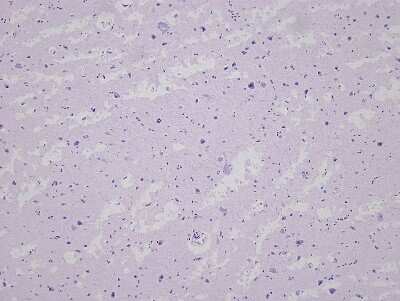

8 results for "Brain Postcentral Gyrus Slides and MicroArrays" in Products

Brain Postcentral Gyrus: Slides and MicroArrays